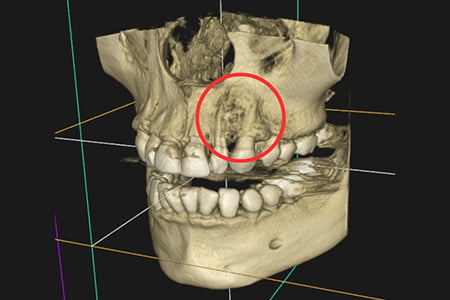

| 症状 | 左上の前歯が急に疼く様になった |

|---|---|

| 治療方針 | 大きな骨欠損を認められる為、精密根管治療を行い骨欠損部位が改善するか経過を追う |

| 治療期間 | 10ヵ月 |

| 治療費用(税込) | ¥468,600 ※2歯分 |

根管治療隠された根管を見逃さないために、高解像度の歯科用CTで診断を行います。その後、視野を20倍以上に拡大可能な歯科専用顕微鏡のマイクロスコープで直接歯の中を確認しながら、超弾性を持ち、根の形に合わせてしなやかに曲がり折れにくいニッケルチタンファイルを用いて根の中を徹底的に清掃していきます。 |